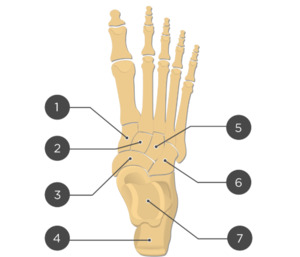

Two unlabeled illustrated images, figures 1 and 2, of the foot and one unlabeled x-ray image, figure 3, were selected. Each image was inputted into ChatGPT Version 4o and the model was prompted to identify the bones depicted in each image using the following prompt.

Prompt 2: ‘Identify the structures labeled in this image’

Two prompts were entered into ChatGPT (Prompt 1: “Make me a picture of human foot with the bones labeled”, Prompt 2: “Identify the structures labeled in this image”). Results of prompt 1, seen in figure 4, are that the generated image was detailed and visually appealing, correctly displaying a foot with visible bones as requested. However, the labeling is entirely inaccurate, with misspelled anatomical terms, misplaced labels, and several missing bones, including the phalanges of the 4th toe. The result of prompt 2 for the first illustrated image is 27% accurate with 3 of 11 bones accurately identified as shown in table 1. The result of prompt 2 for the second illustrated image is 57% accurate with 4 of 7 bones accurately identified as shown in table 2. The result of prompt 2 for the x-ray image is 0% accurate with 0 of 19 structures accurately identified as shown in table 3.

Out of 11 labels, 3 were identified correctly, resulting in an accuracy of 27%.

The output from ChatGPT v4o of prompt 1 "‘Make me a picture of human foot with the bones labeled’ demonstrates a visually appealing and detailed depiction of a human foot with visible bones. However, the labeling is inaccurate, with anatomical terms misspelled, labels misplaced, and several key bones, such as the phalanges of the 4th toe, completely missing. Prompt 2 reveals varying accuracy between the 3 images used: 27% for the first illustrated image, 57% for the second illustrated image, and 0% accuracy for the x-ray image.